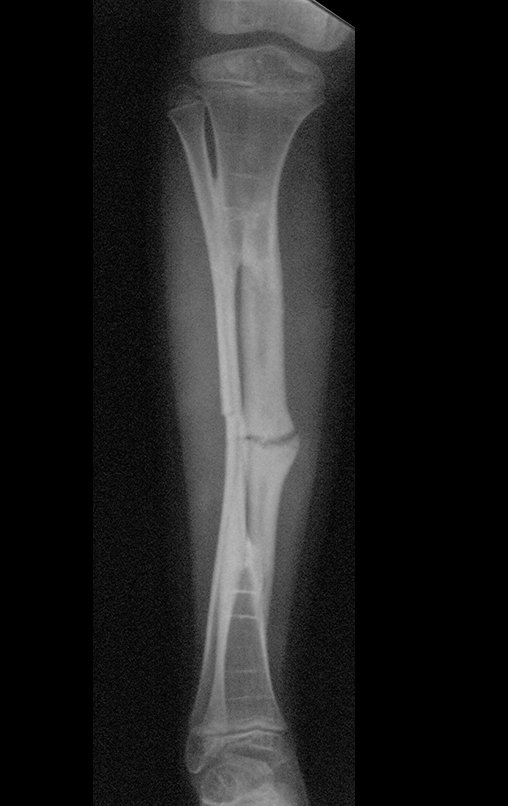

Osteofibrodysplasia – Fibula tibialization technique – Combined autologous and homologous graft reconstruction technique

The patient returns to the office six weeks after surgery, figures 100 to 102 and video 1